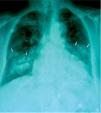

Bronquiolitis obliterante con neumonía organizada inducida por amiodarona: presentación de dos casos con diferente abordaje terapéutico

Bronchiolitis obliterans with organized pneumonia secondary to amiodarone: presentation of two cases with different therapeutic approach